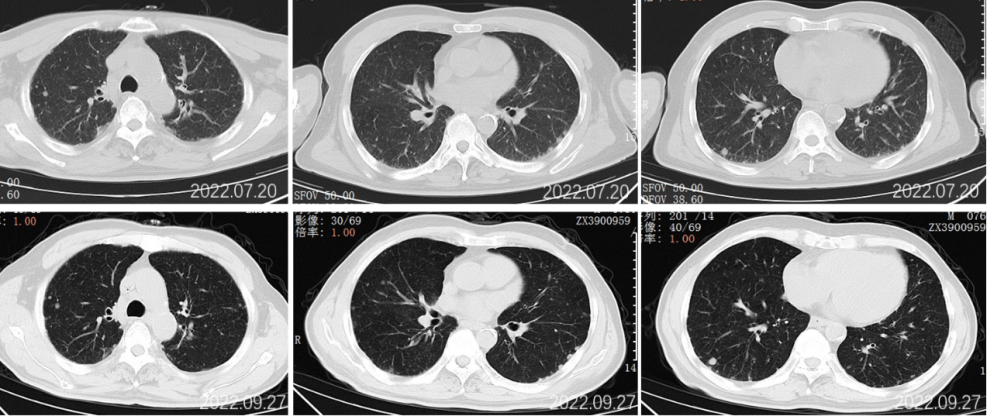

2022.07.20胸部CT示:两肺多发小结节,考虑转移;两侧胸腔少量胸腔积液。头颅MR、骨ECT未见明显异常。

2022.09.27胸部CT平扫:1.两肺多发小结节、类结节影,较前相似,转移性考虑;2.两侧胸腔少量积液较前已吸收。3.左侧第5后肋骨质破坏。

2022.11.25胸部CT平扫:对比2022-09-27影像:1.新见两肺多发间质性肺炎样改变,感染考虑,VP-RADS 2类;2.两肺多发小结节、类结节影,部分较前略缩小,转移性考虑;3.左侧第5后肋骨质破坏,相仿。